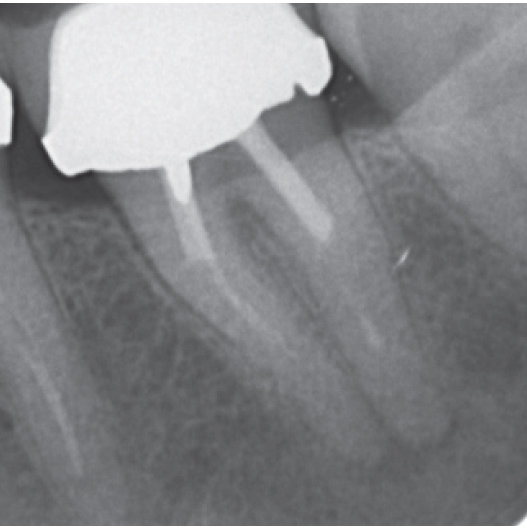

Before

Before Root Canal treatment